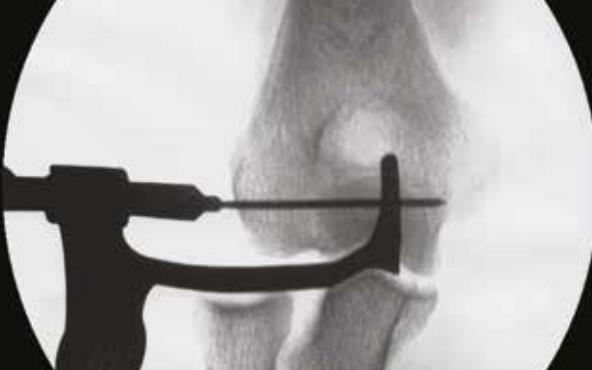

• Fluoroscopic confirmation

• confirm that the Guide Wire (1.5mm K-wire) has been inserted to the correct depth and that the axis of rotation has been properly established using fluoroscopy

• Final fluoroscopic confirmation

• confirm that the reduction is maintained through the full ROM using fluoroscopic imaging